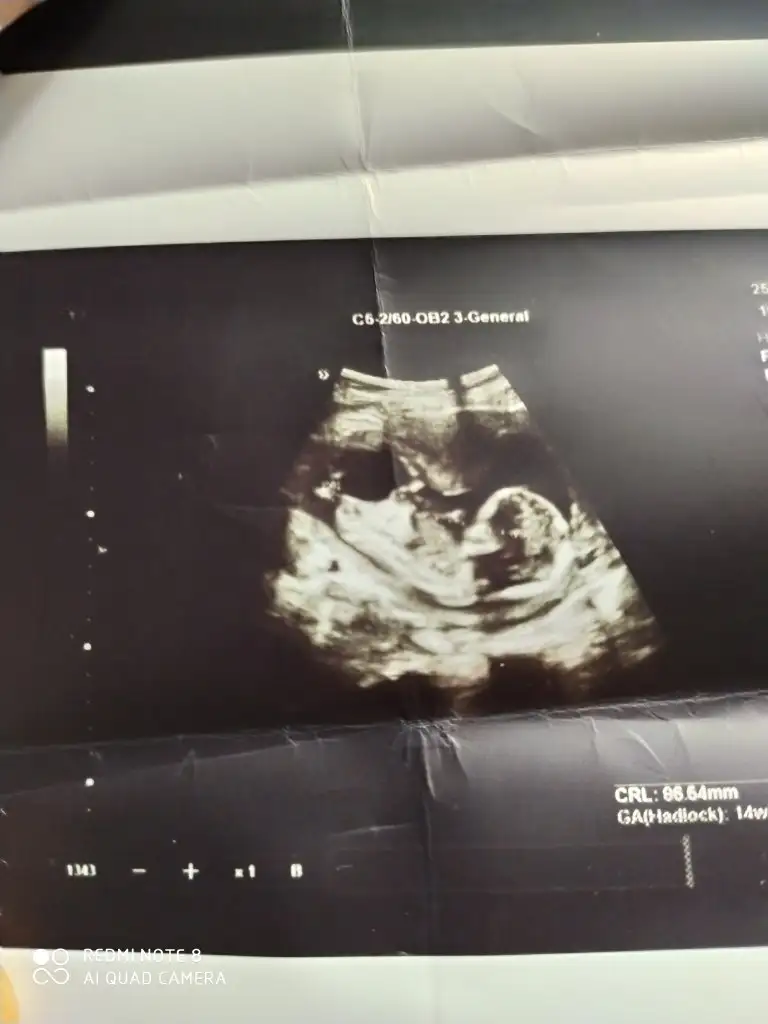

Hayirli sağlıklı olsun.dr mu soyledi.usg paylasmistin degil mi burada.gelecegi parlak cok sansli olsun bebegin.Benim ki. Kız kesin

Evet Dr söyledi teşekkürlerHayirli sağlıklı olsun.dr mu soyledi.usg paylasmistin degil mi burada.gelecegi parlak cok sansli olsun bebegin.

Ben de kız demistim .o haftalik ultrason kaginda daha belli oluyor cinciyet tahmini.çıkınti paralel oldugu icin kız demistim ben de.buradaki fotoda net belli sizin.seni çok iyi anlıyorum.benim de iki kızım var.ve ücuncuyu istiyoruz.olmadi 5 aydir gebelik.hayırlısı olsun.saglikli olsun en önemlisi.Rabbimin vardır bildiği .verdiyse en hayırlısını vermistir.gönlünü ferah tut .Evet Dr söyledi teşekkürlerEki Görüntüle 2764435

Ama çoğu kişi erkek bu bebek diyorBen de kız demistim .o haftalik ultrason kaginda daha belli oluyor cinciyet tahmini.çıkınti paralel oldugu icin kız demistim ben de.buradaki fotoda net belli sizin.seni çok iyi anlıyorum.benim de iki kızım var.ve ücuncuyu istiyoruz.olmadi 5 aydir gebelik.hayırlısı olsun.saglikli olsun en önemlisi.Rabbimin vardır bildiği .verdiyse en hayırlısını vermistir.gönlünü ferah tut .

Ben de kız demistim .o haftalik ultrason kaginda daha belli oluyor cinciyet tahmini.çıkınti paralel oldugu icin kız demistim ben de.buradaki fotoda net belli sizin.seni çok iyi anlıyorum.benim de iki kızım var.ve ücuncuyu istiyoruz.olmadi 5 aydir gebelik.hayırlısı olsun.saglikli olsun en önemlisi.Rabbimin vardır bildiği .verdiyse en hayırlısını vermistir.gönlünü ferah tut .